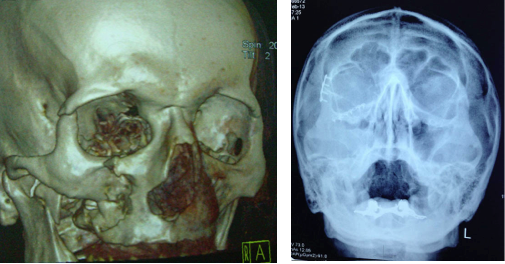

Η ιδιαιτερότητα των οστών του κρανίου και κυρίως του σπλαχνικού ως υμενογενή, προσδίδουν την ανάγκη για άμεση και γρήγορη όσο το δυνατόν αντιμετώπιση, λόγω της συντομότερης πόρωσής τους από τα άλλα οστά του ανθρώπινου σκελετού. Η καθυστέρηση χρονικά στην αντιμετώπιση των καταγμάτων του σπλαχνικού κρανίου, θα οδηγήσει πιθανόν σε φλεγμονές με αποστήματα, κακή πόρωση, ψευδάρθρωση, αδυναμία μάσησης και οδοντικής σύγκλισης, ασυμμετρία και παραμόρφωση του προσώπου, υπαισθησίες ή παραισθησίες νεύρων του προσώπου, κακή ανάταξη των καταγμάτων με πιθανή υποτροπή τους.

Επίσης Τα τελευταία χρόνια, αυξημένος παρουσιάζεται ο αριθμός των αυτόματων καταγμάτων σε ασθενείς που λαμβάνουν φάρμακα (διφοσφωνικά) για την οστεοπόρωση ή την οστεοπενία, αλλά και σε ασθενείς που λαμβάνουν θεραπείες για νεοπλάσματα (πχ χημειοθεραπείες). Γίνεται λοιπόν κατανοητό, πόσο σημαντική είναι η όσο το δυνατόν γρηγορότερη χρονικά παρέμβαση με ανάταξη των οστών του σπλαχνικού κρανίου σε περίπτωση καταγμάτων του.

Οι τεχνικές οστεοσύνθεσης με μικρού μεγέθους πλάκες είναι σήμερα οι πλέον συνήθης. Μεταλικές ή και απορροφήσιμες πλάκες τοποθετούνται ανάλογα με την περίπτωση του κατάγματος. Πολλές φορές χρειάζεται και δεύτερη παρέμβαση, λόγω καθυστερημένης χρονικά ανάταξης του κατάγματος, για τη διόρθωση της όχι καλής πόρωσης ή σύγκλισης του τραύματος, με χρήση διαφόρων ιστών όπως οστικό μόσχευμα από το κρανίο ή το ανώνυμο οστό. Με το πλεονέκτημα της καλής γνώσης των οστών του κρανίου το αποτέλεσμα είναι στην πλειονότητα το ευνοϊκότερο.